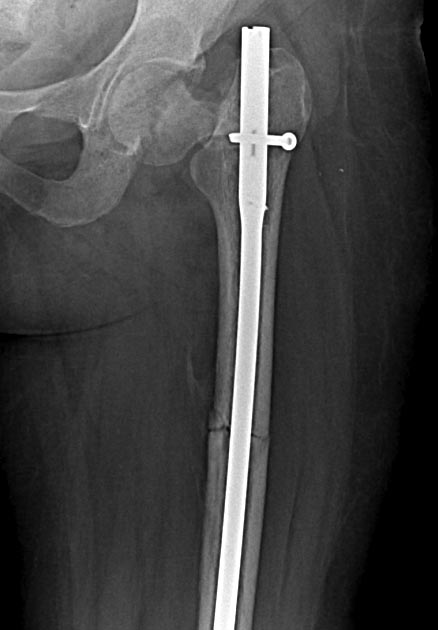

Доброго времени суток. За правый (с винтами) надо бороться. Вальгизирующая остеотомия позволит и перелом срастить и скомпрометированный участок головки выведет из под нагрузки. А вот с другой стороны (с гвоздем) перспективы сохранения головки сомнительные, тем более на таком сроке. Головка резко порозная. Тут можно дождаться консолидации диафиза и протезировать потом чем угодно.

Я за два протеза. на мой взгляд, остеотомия - здесь не лучший вариант, скорее всего слишком мало контакта в зоне перелома. Здесь ведь нет по сути варусного коллапса, скорее сдвиг и ротация, какой будет ШДУ после остеотомии, близкий к 180? Скорее всего получим тугой ложный сустав с ожидаемыми проблемами при протезировании. Что касается левой половины, то все варианты уже обсудили. Единственное, не стал бы рассматривать ревизионные ноги в принципе (возраст!) и Proxima (от нее вроде сами DePuy отказались), для остеосинтеза можно использовать пластину для перипротезных переломов (у Zimmer есть симпатичная)

О коротких ножках впечатления скорее положительные, большей частью выживают нормально,если правильно выбирать показания, правда сроки наблюдения пока небольшие, чаще всего лет 5. В этом случае я бы не рискнул - конечность была неопорная 5 мес, метафиз явно пострадал, кроме того непонятно, что осталось от шейки.

Добрый вечер, коллеги! по нашему мнению в 27 лет необходимо приложить максимум усилий для сохранения тазобедренных суставов, эндопротезирование выполнить никогда не поздно. вальгизирующая остеотомия не усложняет протезирование. Справа вальгизация и клинок - проблем не будет, слева необходима открытая репозиция и реконструкция с вальгизирующей остеотомией и фиксацией клинковой пластиной. снимок "страшный" на первый взгляд, за счет ротации.перелом скорее латеральный, по истечению 5 мес головка имеет полный объем и структуру сходную с костями таза. Вероятнее всего она жизнеспособна, достоверно подтвердить сохранение кровоснабжения возможно при выполнении селективной ангиографии. использование коротких ножек слева недопустимо по одной простой причине: все короткие ножки подразумевают остеотомию по краю хряща головки, а опора ножки должна равномерно распределяться на дугу Адомса, медиальный и дистальный кортикалы в/3 диафиза и верхний край шейки бедренной кости. поэтому слева возможен вариант ретроградного штифтования и клинковой пластины, технически сложно но возможно. остеотомия на штифте - сомнительное занятие, даже в умелых руках очень много проблем, а убедительных результов пока не опубликовано, ставить эксперименты в 27 лет даже на основании квот .....!? лучше идти проверенным путем. с уважением Ушаков С.А.